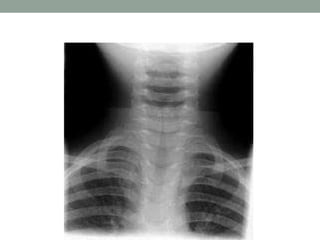

1. Bé gái 8 tháng bệnh 2 ngày ho, sốt nhẹ. Khám: môi

hồng, khàn tiếng, thở rít hít vào, sốt nhẹ, phổi thô, thở

không kéo hô hấp, XQ phổi thẳng hình ảnh nóc nhà

thờ(Steeple sign).

• Hội chứng gì?

• Chẩn đoán?